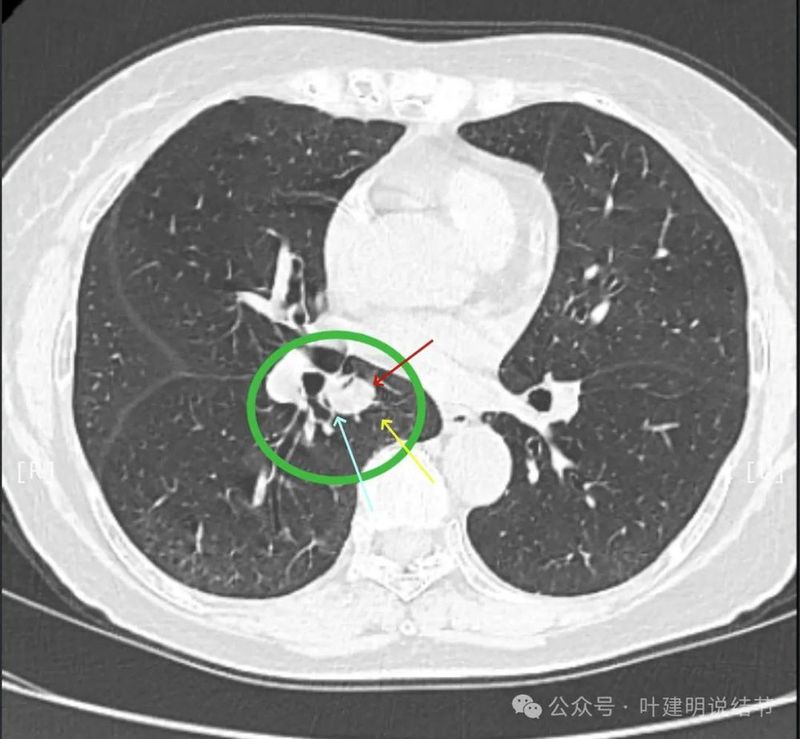

病灶密度较为均匀,对支气管是压迫后移位。表面光滑。

似乎有血管穿过。

边缘光滑,没有毛刺,膨胀性生长。

表面光滑,内部密度较均匀,边界清楚,膨胀性长。

没有侵犯邻近支气管。

边缘光滑,分叶不明显。

上图这个层面感觉病灶与肺血管之间没有明显间隙,似像侵犯或愈着的样子。

结节边缘区域与血管之间又有间隙了的。

下肺静脉水平,病灶基本没有了。